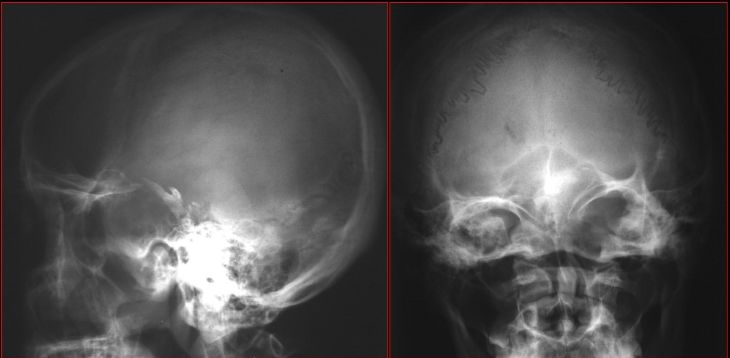

慢性鼻窦炎—平片改变

平片及CT检查表现

Water氏位:窦腔混浊,液平面